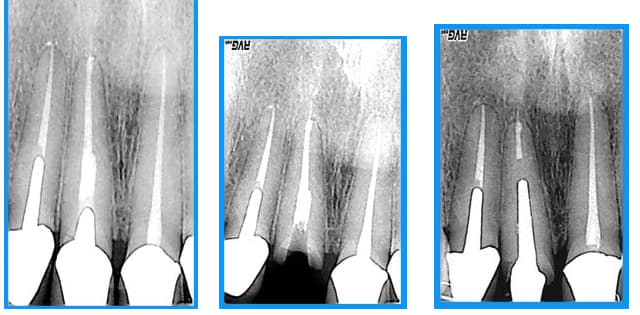

curieux de voir que le dépassement a suivi la dent... serait un instrument cassé?

Dépassement dt5hca - Eugenol

et l'interrogation de spriford? je me pose la même question.

aucune idée

la patiente a en bouche des ceramiques faites depuis plus de 15 ans(made in USA)avec les traitements s'y référents

seule la 11 a cassée(due au deplacement de l'antagoniste? peut être,sans doute)

je ne me suis pas acharnée à retirer le cône noyé ds la pâte(acryl? ou thermafill mais cela existait il à l'epoque?) vu l'absence d'image apicale et.... le fait que je n'y suis pas arrivée:)

tort? raison?

on verra mais à un an 1/2(IC et prov posés en nov 2005) pas gd chose ne se passe

oui, c'est visiblement bien toléré, juste frustrant de ne pas savoir, filet de ciment? cone? en tous cas, ça suit la dent.